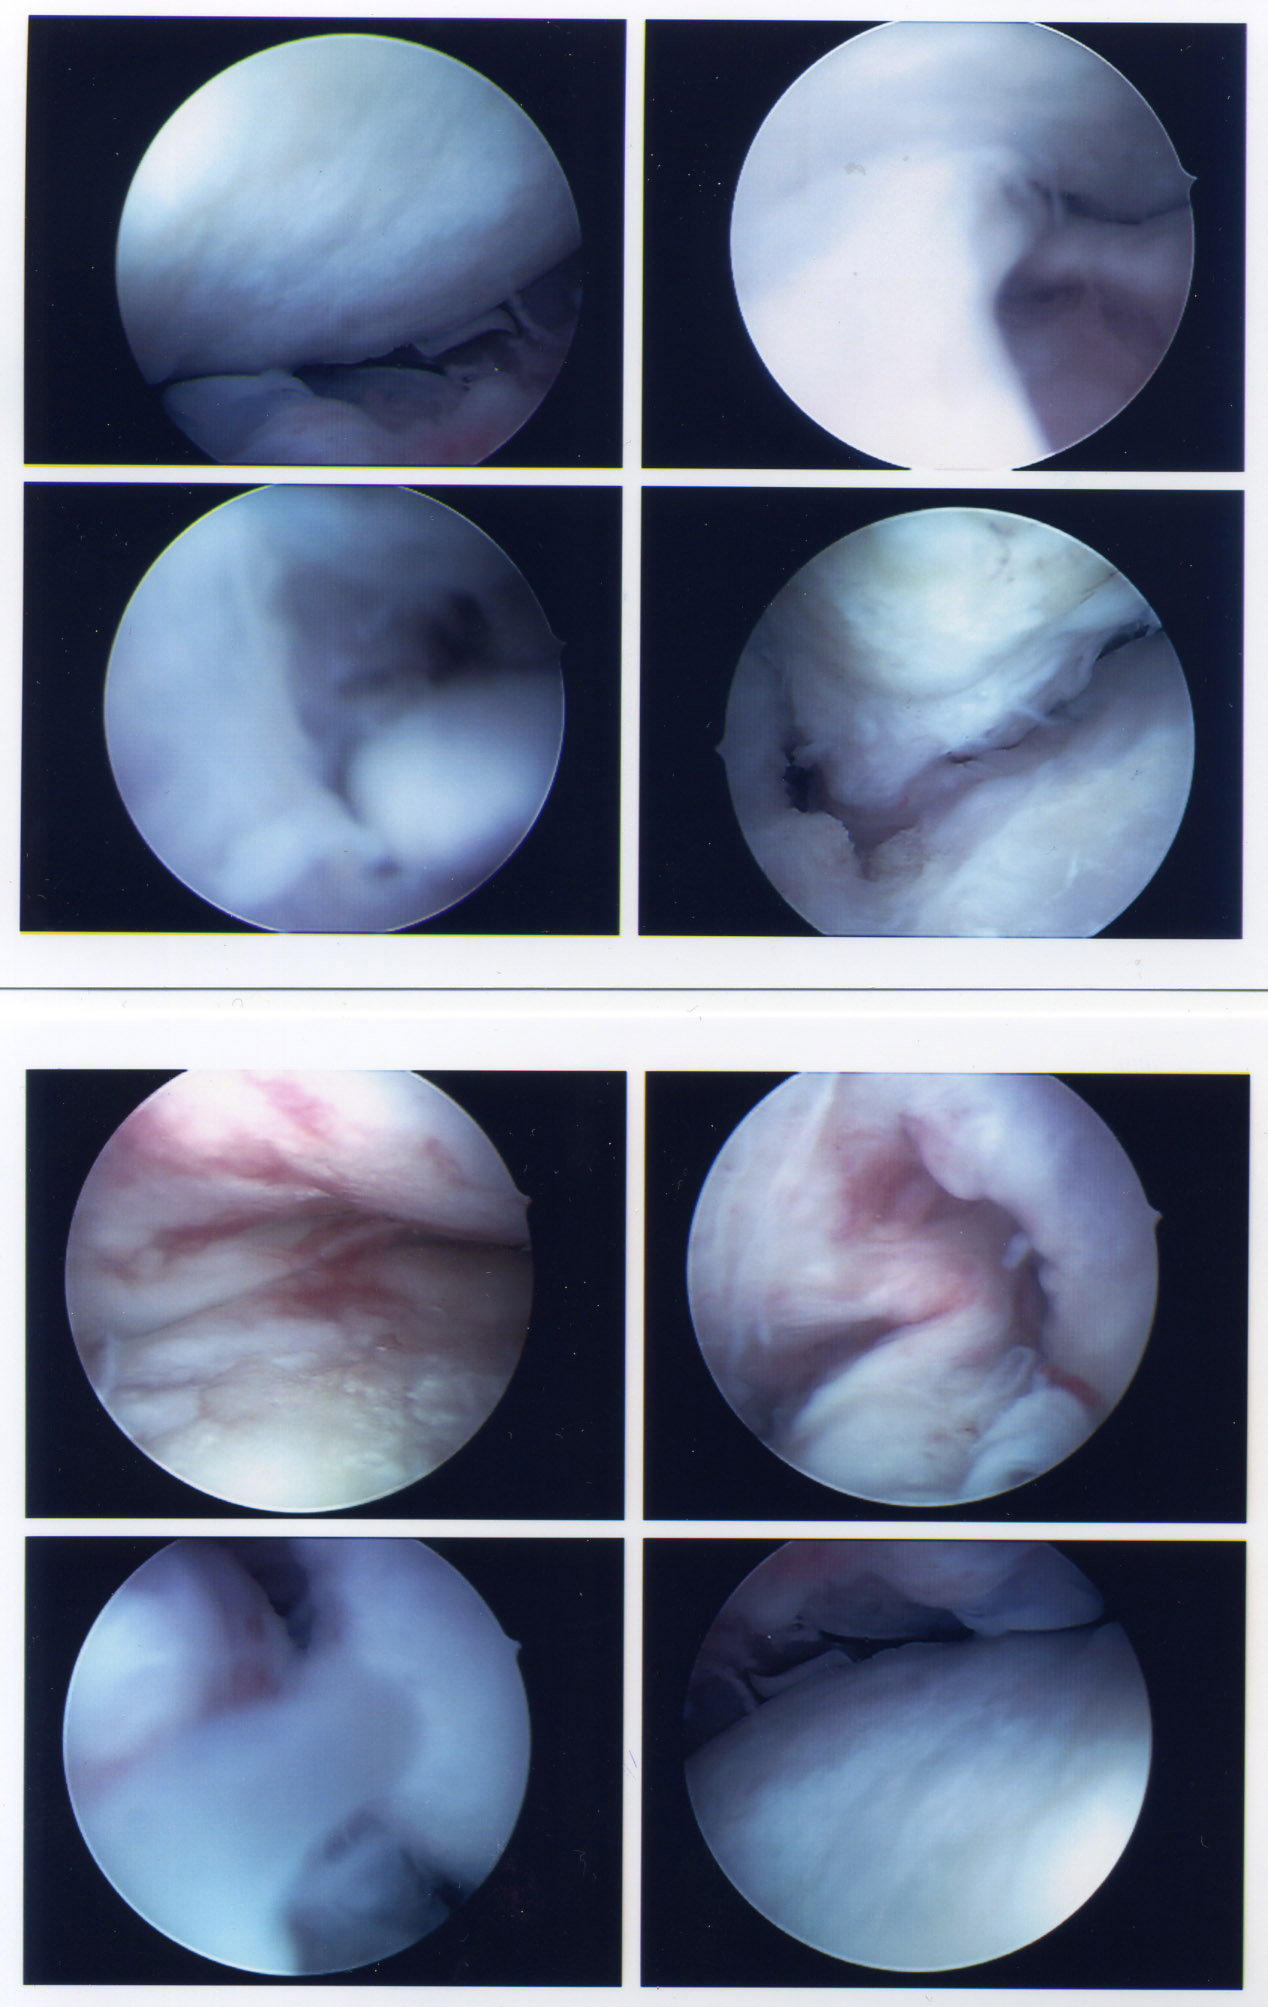

Anlässlich der Arthroskopie wurden ein paar Osteophyten entfernt und alles ein wenig geglättet - besonders Extrahiert! - Klicken für grössere Fassunggut siehts im Gelenk nach wie vor nicht aus. Aber die Streckung sollte nun etwas besser sein, nachdem das Teilchen rechts im Bild draussen ist.

Und wer will, kann sich hier noch die Fotos aus dem Inneren anschauen - klicken für grössere Fassung:

Arthsoskopiefotos 9. Mai 2008; Klicken für grosse Fassung

Ausser dass ich fleissig Narbensalbe schmiere und Kraftübungen mache, ist wieder der Alltag eingekehrt - schon 18 Tage nach dem Eingriff wanderte ich leicht über die schottischen Highlands, wenig später lange durch Berlin, und auch wenn das Knie auf solche Anstrengungen noch etwas gereizt reagiert - ausser dem üblichen "Ziepen" und einem Schmerz bei Druck auf den Bereich zwischen Patella und Tuberositas ist alles OK. Gut so. Inzwischen weiss ich dank dem Ops-Bericht auch, dass nebst der Metallentfernung während der Arthroskopie ein Ventraler Tibia-Osteophyt (VTO) entfernt und einige weitere Blockaden behoben wurden.